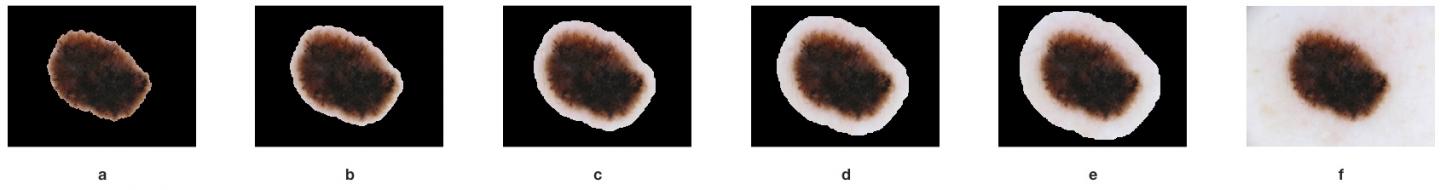

To test their hypothesis, the researchers first compared the effects of no segmentation, full segmentation, and partial segmentation on classification and demonstrated that partial segmentation led to the best results. They then proceeded to determine how much segmentation would be "just right." To do that, they used three degrees of partial segmentation, investigating how a variable-sized non-lesion border around the segmented skin lesion affects classification results. They performed comparisons in a systematic and reproducible manner to demonstrate empirically that a certain amount of segmentation border around the lesion could improve classification performance.

Their findings suggest that extending the border beyond the lesion to include a limited amount of background pixels improves their classifier's ability to distinguish melanoma from a benign skin lesion.

"Our experimental results suggest that there appears to be a 'sweet spot' in the degree to which the surrounding skin included is neither too great nor too small and provides a 'just right' amount of context," said Marques.